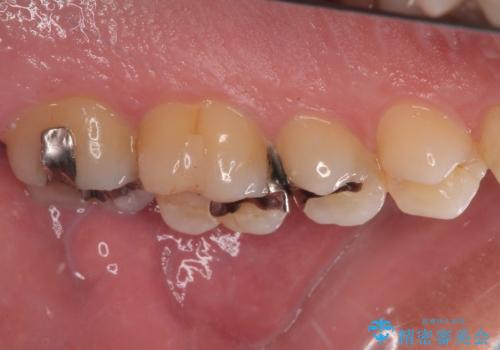

放置した欠損部 奥歯の即時荷重インプラント治療

左下の欠損部を長期間欠損を放置していたことで、咬み合う上の奥歯が動いてしまっている状態でした。

インプラント部は埋入とともに仮歯を装着し、同時に上顎奥歯の部分矯正を開始することとしました。

理想的な咬み合わせに改善した上で、インプラント補綴治療を行うこととしました。

部分矯正を行ったこと治療期間は長くなりましたが、違和感のない咬み合わせを達成することができました。